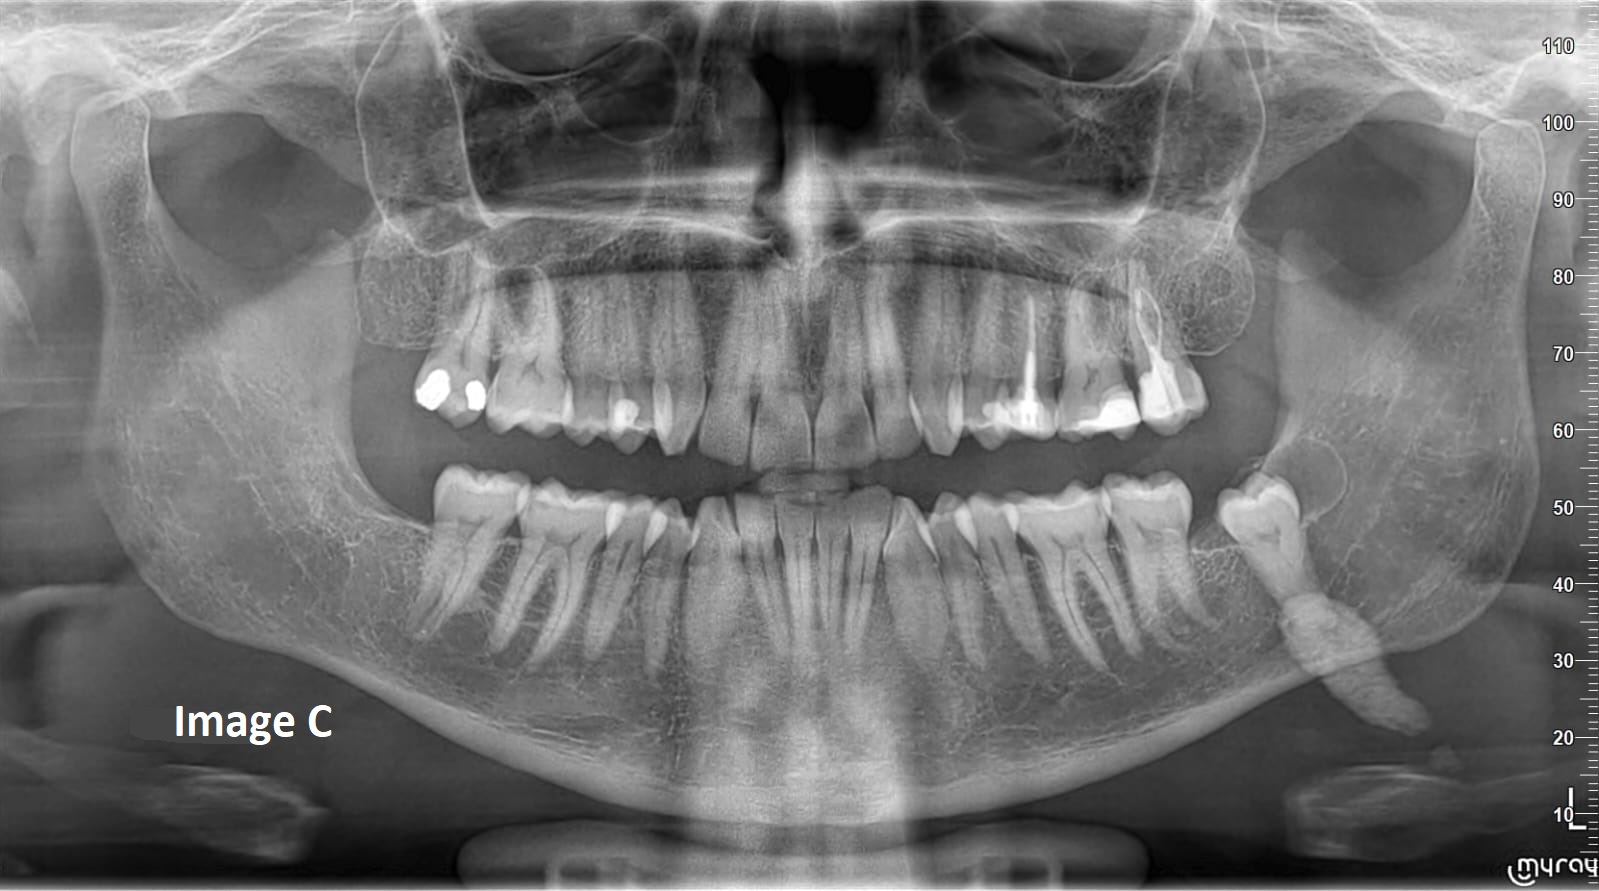

QUIZ 4QUIZ 4Which of the following would you include in your differential diagnosis? (Select one or more correct answers) Which of the following would you include in your differential diagnosis? (Select one or more correct answers)a. Compound Odontomab. Complex Odontomac. Periapical Cemento-Osseous Dysplasia d. Cemento-Ossifying Fibromae. CementoblastomaQUIZ 4Which of the following would you include in your differential diagnosis? (Select one or more correct answers) Which of the following would you include in your differential diagnosis? (Select one or more correct answers)a. Degenerative Arthritisb. Rheumatoid Arthritisc. Osteochondromad. Metastatic Tumore. Aneurysmal Bone CystQUIZ 4Describe your findings from this panoramic radiograph. Describe your findings from this panoramic radiograph.